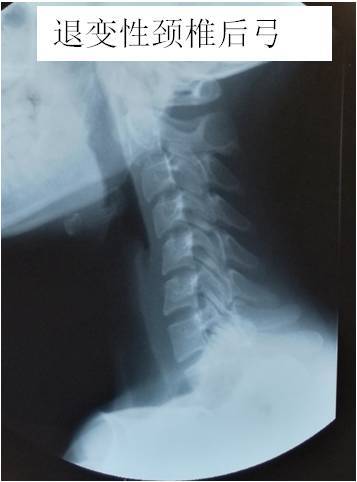

· 颈椎曲度反弓只是提示局部地方有退变,需要根据具体的症状做相应的处理。 如果是伴随颈部的地方疼痛和僵硬,可以选择按摩和热敷;另外就是可以选择药物比如替扎尼定,还可以选择一些膏药比如消痛贴膏有助于缓解。 如果是伴随上肢的麻木等不舒服,那么还可能是压迫了神经根,最好是完善颈部的磁共振检查,可以更为准确的判断病情。 平时要注意个人 · 知道颈椎反弓的成因,接着对因下药。 如果已经颈椎反弓了,可以适当地做一些牵引治疗。 如果病情较轻,通常采用坐位牵引,除此之外,还可以使用卧位牵引,可以在专业人士的指导下适当地借助一些工具,牵引的过程中,要注重牵引的强度,角度,时间以及重量。1510 · 颈椎反弓 一种常见颈椎病。颈椎有正常的生理弯曲,如果没有生理弯曲,甚至向相反的方向弯曲,称为反弓。 人类属于高级脊椎动物,颈椎"c"形向前的生理弧线保证了颈椎活动的高度灵活性,但人们常常发生违背颈椎生理曲线的姿态和活动。

1915 · 第一,颈椎反弓是一种普遍颈椎病。 颈椎骨有一切正常的生理弯曲,要是没有生理弯曲,乃至向反过来的方位弯折,称之为反弓。 颈椎反弓是组成颈椎病最常见的病理基本,而不适度用枕是造成 颈椎反弓的关键原因。 第二,颈椎反弓的严重后果: 颈椎反弓会造成许多 病症。 最先是颈椎骨主动脉受力,会造成大脑供血不足,次之是神经受力,造成神经根占位1 问: 颈椎反弓有什么后果,要怎么办 答: 颈椎反弓是会造成全身性的不正常的疾病。对人的危害极大。颈椎生理曲度变直或者颈椎生理曲反弓而造成颈椎管狭窄,挤压了脊髓而出现呕吐,眩晕,易昏撅摔倒而发生危险。脊髓病例一: 病情描述 颈椎曲度反弓如何解决颈椎曲度反弓如何解决 问题回答 病情分析:你好,预防颈椎病主要是减缓颈椎间盘退变的进程不良睡眠体位,工作姿势不当,不适当的体育锻炼都是颈椎骨关节退变的常见原因指导